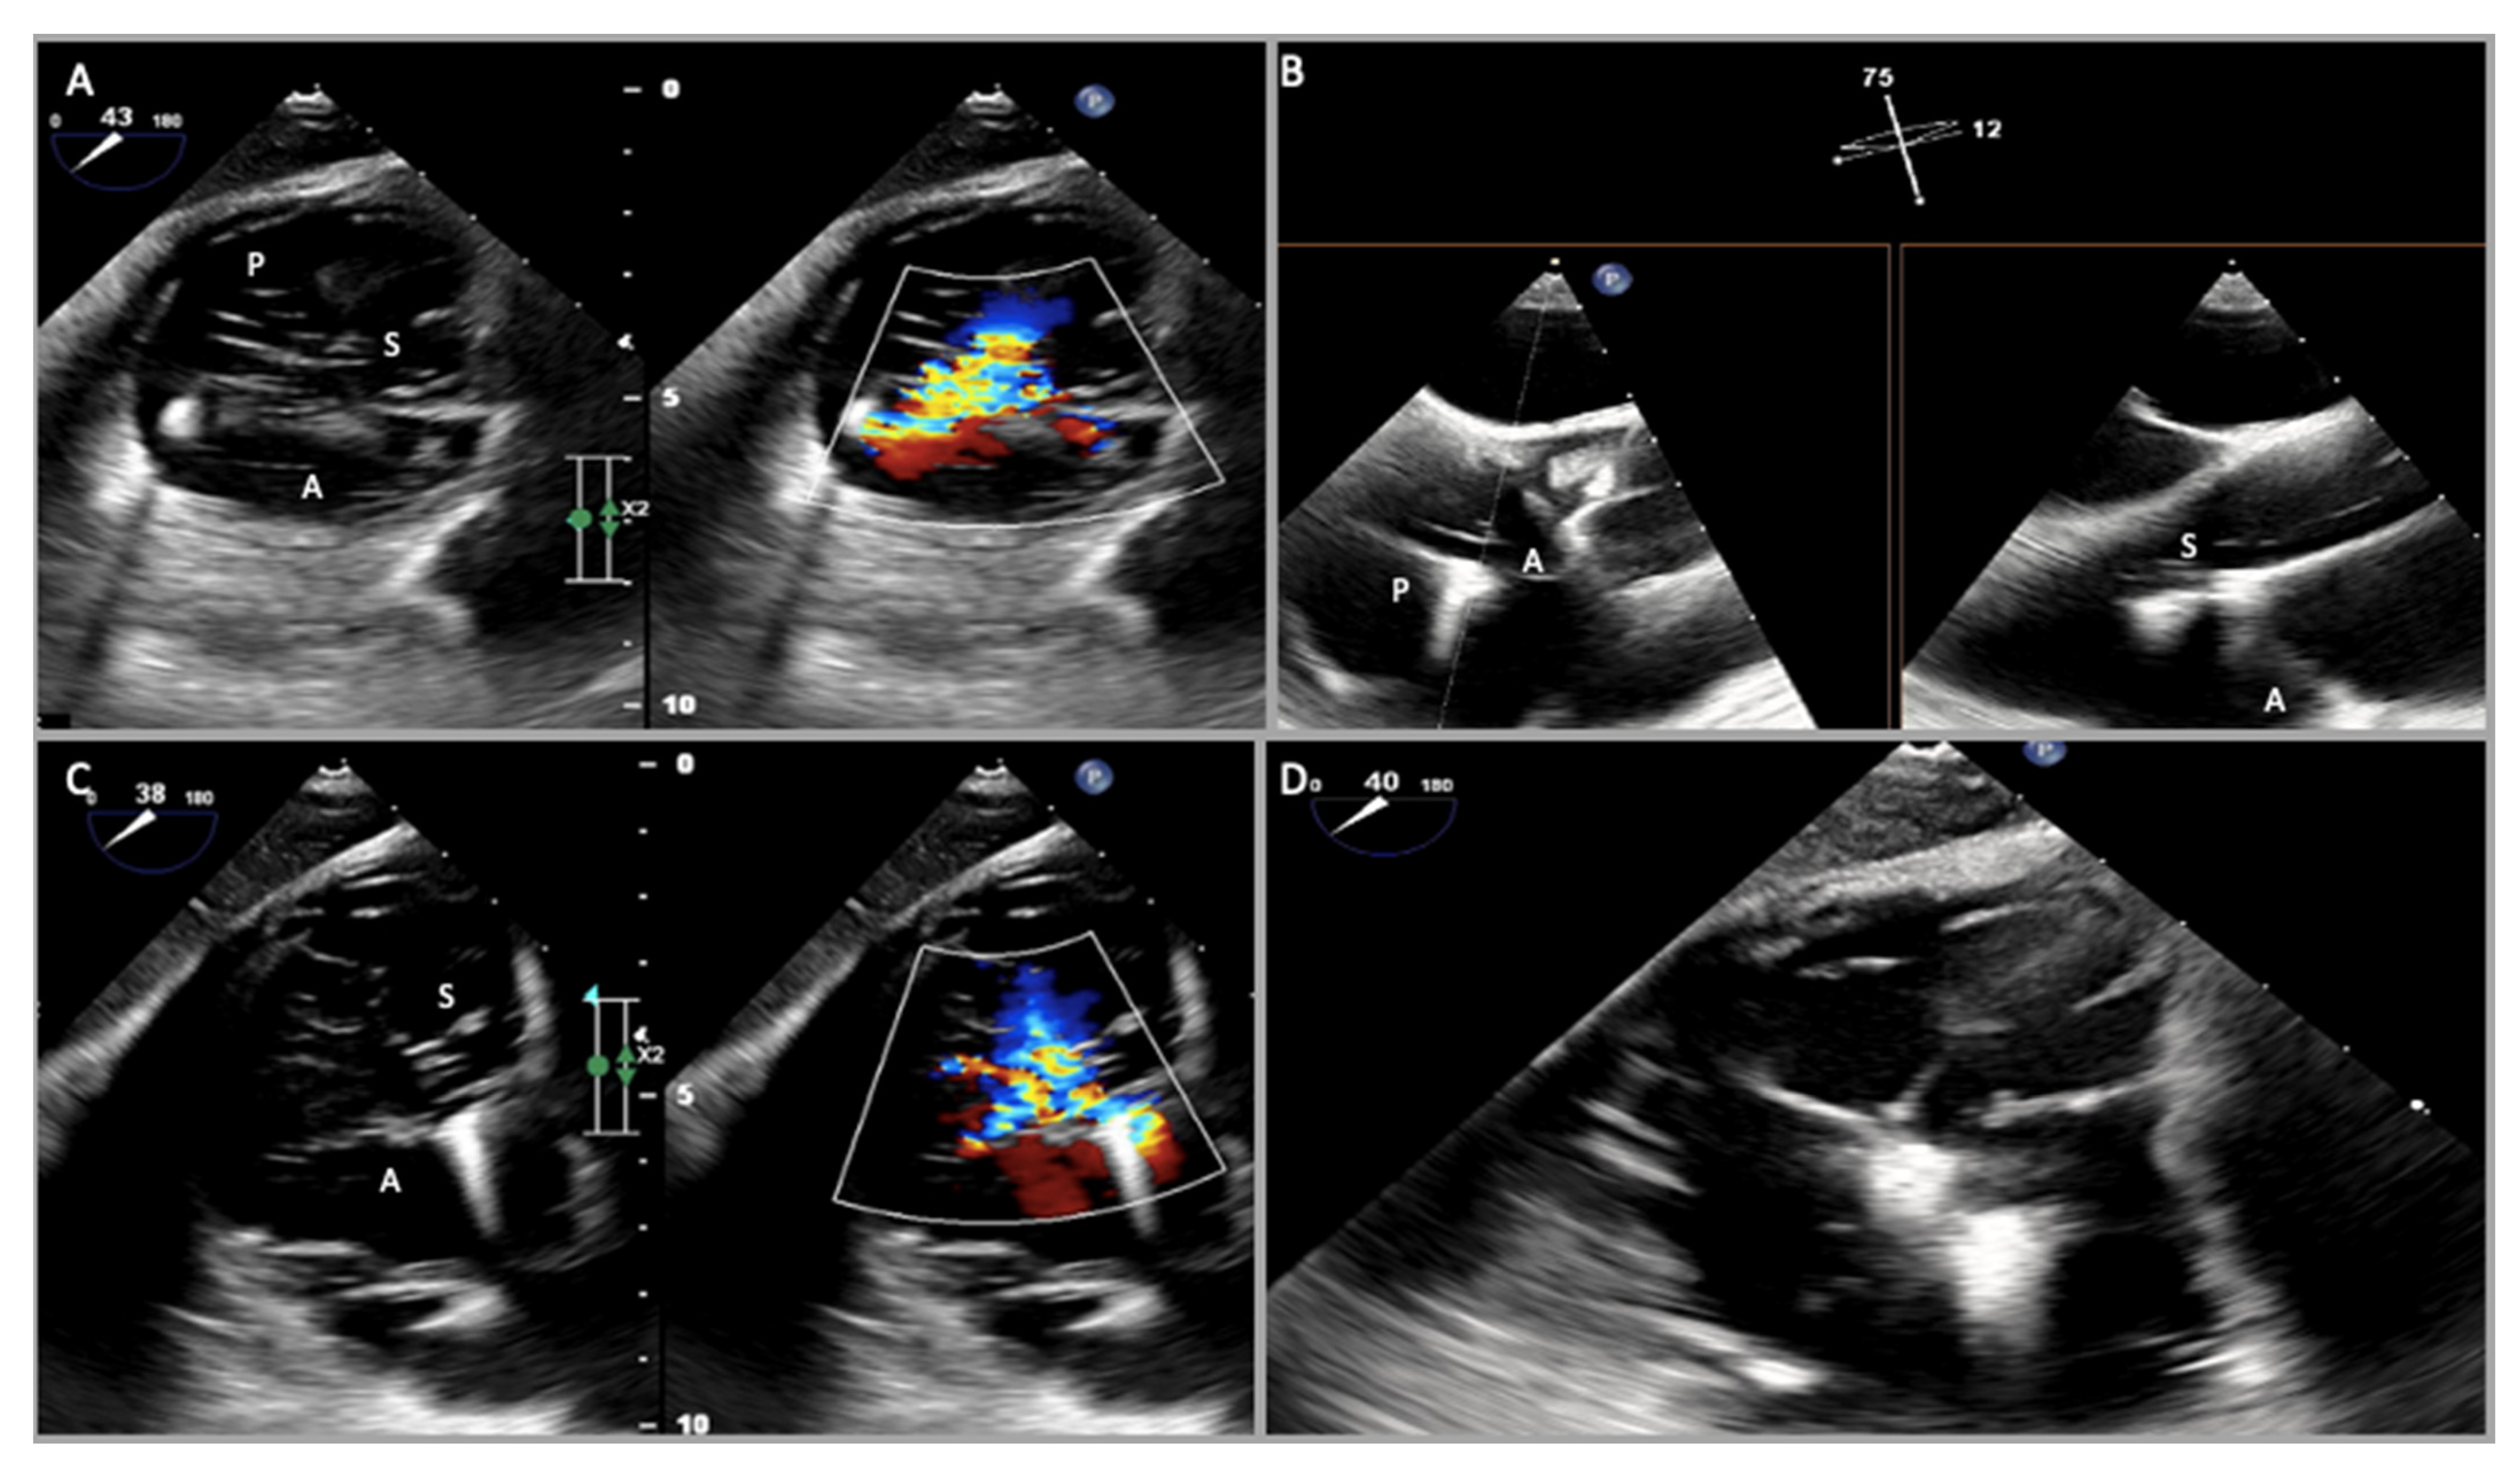

2.1. Two-Dimensional and Three-Dimensional Transthoracic and Transesophageal Echocardiography

- Prihadi, E.A.; Delgado, V.; Hahn, R.T.; Leipsic, J.; Min, J.K.; Bax, J.J. Imaging Needs in Novel Transcatheter Tricuspid Valve Interventions. JACC Cardiovasc. Imaging 2018, 11, 736–754. [Google Scholar] [CrossRef]

- Spinner, E.M.; Lerakis, S.; Higginson, J.; Pernetz, M.; Howell, S.; Veledar, E.; Yoganathan, A.P. Correlates of Tricuspid Regurgitation as Determined by 3D Echocardiography: Pulmonary Arterial Pressure, Ventricle Geometry, Annular Dilatation, and Papillary Muscle Displacement. Circ. Cardiovasc. Imaging 2012, 5, 43–50, Erratum in Circ. Cardiovasc. Imaging 2012, 5, e54. [Google Scholar] [CrossRef]

- Lang, R.M.; Badano, L.P.; Tsang, W.; Adams, D.H.; Agricola, E.; Buck, T.; Faletra, F.F.; Franke, A.; Hung, J.; de Isla, L.P.; et al. EAE/ASE Recommendations for Image Acquisition and Display Using Three-Dimensional Echocardiography. J. Am. Soc. Echocardiogr. 2012, 25, 3–46. [Google Scholar] [CrossRef] [PubMed]

- Hahn, R.T.; Saric, M.; Faletra, F.F.; Garg, R.; Gillam, L.D.; Horton, K.; Khalique, O.K.; Little, S.H.; Mackensen, G.B.; Oh, J.; et al. Recommended Standards for the Performance of Transesophageal Echocardiographic Screening for Structural Heart Intervention: From the American Society of Echocardiography. J. Am. Soc. Echocardiogr. 2021, 35, 1–76, Erratum in J. Am. Soc. Echocardiogr. 2022, 35, 447. [Google Scholar] [CrossRef] [PubMed]

- Sugiura, A.; Tanaka, T.; Kavsur, R.; Oeztuerk, C.; Vogelhuber, J.; Wilde, N.; Becher, M.U.; Zimmer, S.; Nickenig, G.; Weber, M. Leaflet Configuration and Residual Tricuspid Regurgitation after Transcatheter Edge-to-Edge Tricuspid Repair. JACC Cardiovasc. Interv. 2021, 14, 2260–2270. [Google Scholar] [CrossRef] [PubMed]

- Carpenito, M.; Cammalleri, V.; Vitez, L.; De Filippis, A.; Nobile, E.; Bono, M.C.; Mega, S.; Bunc, M.; Grigioni, F.; Ussia, G.P. Edge-to-Edge Repair for Tricuspid Valve Regurgitation. Preliminary Echo-Data and Clinical Implications from the Tricuspid Regurgitation IMAging (TRIMA) Study. J. Clin. Med. 2022, 11, 5609. [Google Scholar] [CrossRef]

- Agricola, E.; Asmarats, L.; Maisano, F.; Cavalcante, J.L.; Liu, S.; Milla, F.; Meduri, C.; Rodés-Cabau, J.; Vannan, M.; Pibarot, P. Imaging for Tricuspid Valve Repair and Replacement. JACC Cardiovasc. Imaging 2021, 14, 61–111. [Google Scholar] [CrossRef]

- Ancona, F.; Stella, S.; Taramasso, M.; Marini, C.; Latib, A.; Denti, P.; Grigioni, F.; Enriquez-Sarano, M.; Alfieri, O.; Colombo, A.; et al. Multimodality imaging of the tricuspid valve with implication for percutaneous repair approaches. Heart 2017, 103, 1073–1081. [Google Scholar] [CrossRef] [PubMed]

- Agricola, E.; Ancona, F.; Stella, S.; Rosa, I.; Marini, C.; Spartera, M.; Denti, P.; Margonato, A.; Hahn, R.T.; Alfieri, O.; et al. Use of Echocardiography for Guiding Percutaneous Tricuspid Valve Procedures. JACC Cardiovasc. Imaging 2017, 10, 1194–1198. [Google Scholar] [CrossRef]